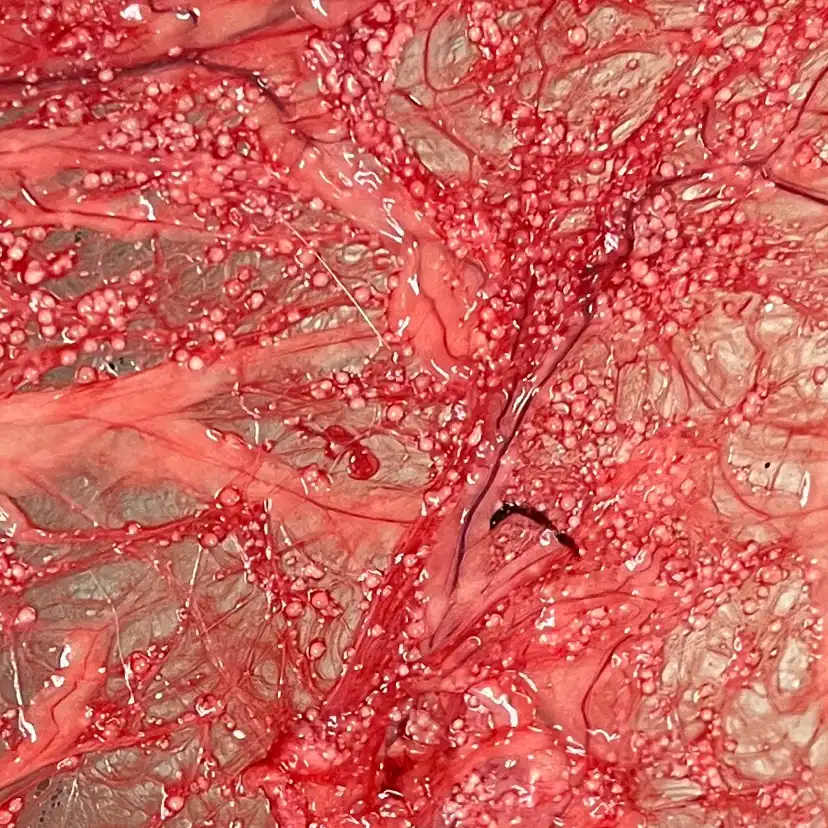

Core-Shell Spherification®

Our patented CSS® encapsulation technology surrounds cells or drugs in protective hydrogel shells, allowing for sustained delivery and better outcomes—no matter the challenge.

The platform is fully customizable, enabling precise control over release timing, bead size, and therapeutic payload for a wide range of applications.